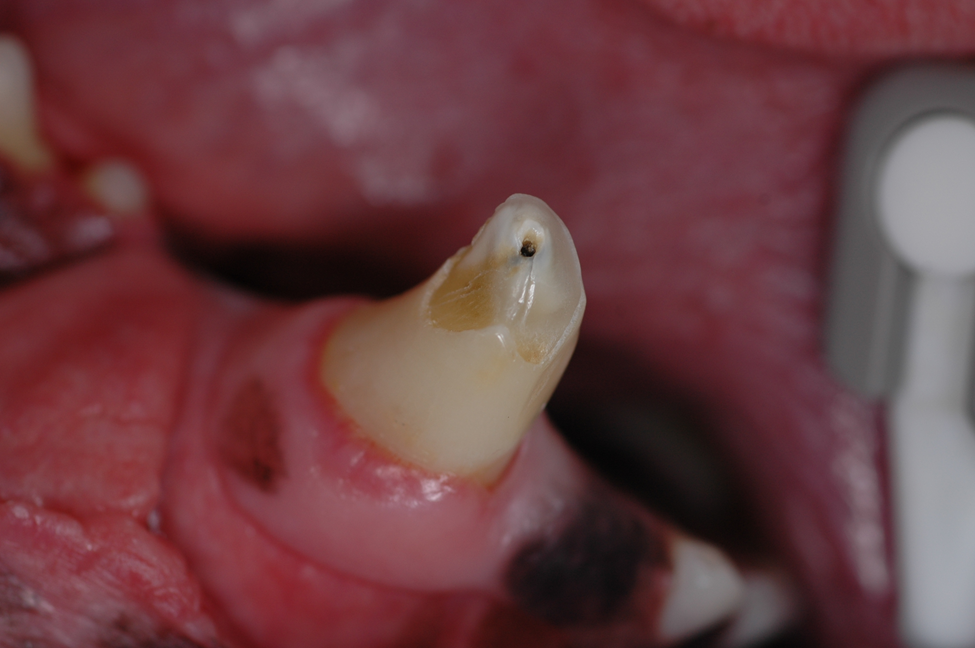

Broken teeth need to be treated immediately.  A tooth that has been broken less than 48 hrs can be saved with a procedure called a “Vital Pulpotomy.”   After 48 hrs., treatment options are root canal therapy or extraction.  Since our pet friends rely heavily on their teeth, saving them is a better and less painful option (root canal therapy).   Leaving a broken tooth in the mouth without treatment causes unnecessary, prolonged oral pain. Finally, a discolored tooth is a dead tooth.  A recent study indicated that 92% of all discolored teeth are non-vital (dead).  Saving those teeth via root canal therapy +/- a crown is highly recommended for those teeth that are deemed strategic (all canine teeth, maxillary 4th premolars and mandibular 1st molar teeth)